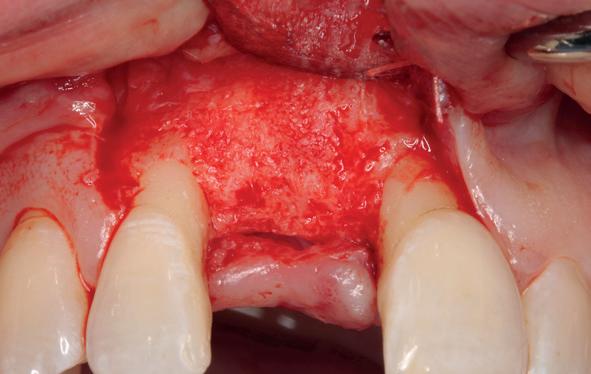

Tijdens de chirurgische behandeling worden na het afschuiven van de flap de posities bepaald van de implantaten met de boorsjabloon. In de bovenkaak worden 7 implantaten geplaatst en in de onderkaak 8

Lateraal van de implantaten wordt de kaak fors uitgebouwd volgens de Hybride GBR-techniek met Oragraft (allograft) van Lifenet die wordt vermengd tot een cocktail met BioOss (xenograft) van Geistlich, autoloog geoogste botsnippers en verzameld bloed uit het wondgebied. De botgraft wordt bedekt met een Ossix (crossed linked) membraan en met Hyadent (hyaluronzuur) overspoten. De sinuslift wordt gelijktijdig met de laterale botopbouw volgens de Caldwell Luc methode uitgevoerd en de uitgeprepareerde holte opgevuld met de botgraft. De flaps worden eerst horizontaal ontlast (gemobiliseerd) en vervolgens naar elkaar toe gehecht met vicryl rapide. Daarbij wordt gebruikgemaakt van horizontale matrassen, zodat de wondranden passief tegen elkaar

komen te liggen en de flaps primair gesloten kunnen worden. Het passief sluiten van een flap voorkomt wonddehiscenties in de genezingsfase die als complicaties kunnen optreden en botregeneratie verstoren. Daarnaast wordt bij een wonddehiscentie het risico op infectie van de graft sterk verhoogd waardoor het gewenste resultaat niet kan worden bereikt. Afstoting van graft materiaal komt dan veelvuldig voor soms gecombineerd met abcesvorming als geen voorzorgsmaatregelen worden genomen. Complicaties moeten daarom nauwlettend gevolgd worden totdat ze verdwenen zijn. De patiënt krijgt na chirurgie postoperatieve instructies en adviezen over de postoperatieve zorg. Daarbij wordt ook de nadruk gelegd op het koelen (coldpack) en zijdelingse druk op de wang. Het blijkt dat koelen en het uitoefenen van druk op het operatiegebied oedeem en hematoomvorming grotendeels kunnen verminderen en soms zelfs kunnen voorkomen.

Twee weken later zie ik de patiënt terug voor controle van de eerste wondgenezing. De noodprothese mag de eerste twee weken niet gedragen worden en wordt tijdens de controle zorgvuldig aangepast aan de nieuwe situatie. Hiervoor wordt de prothese gedeeltelijk uitgefreesd en voorzien van een Soft Reliner materiaal. Te veel druk op de beide kaken moet ten alle tijden voorkomen worden en heeft effect op de ingroei van de botopbouw. De genezingsperiode duurt tenminste zes maanden voordat verdergegaan kan worden met de tweede fase: de abutment chirurgie. Hierbij wordt extra aandacht besteed aan het herstel van de gekeratiniseerde gingiva rondom de abutments. Dit komt ten goede aan de uitvoering van de mondhygiëne en dus de stabiliteit van de peri-implantaire mucosa. Deze ogenschijnlijk eenvoudige behandeling is essentieel voor de prognose van de implantaten op de lange termijn. Te weinig gekeratiniseerde mucosa maakt zelfzorg (borstelen/interdentaal reinigen) vaker pijnlijk of lastig, waardoor plaque en mucositis makkelijker kunnen ontstaan en blijven over de lange termijn. Dat kan bij patiënten die vatbaar zijn voor peri-implantitis zich vertalen naar crestaal botverlies rondom implantaten. Gek genoeg wordt de essentie van het herstellen van de gekeratiniseerde gingiva rondom implantaten regelmatig genegeerd.